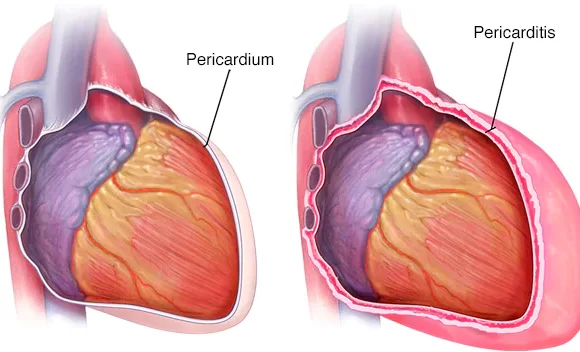

التهاب التامور الحاد هو التهاب يصيب التأمور (الكيس المرن ذو الطبقتين الذي يغلف القلب) الذي يبدأ فجأة ، وغالبًا ما يكون مؤلمًا ، ويسبب دخول السوائل ومكونات الدم مثل الفيبرين وخلايا الدم الحمراء وخلايا الدم البيضاء إلى الحيز التأموري .

في بعض الأحيان ، يمكن أن يتسبب الالتهاب في دخول السوائل الزائدة إلى الحيز التأموري (الانصباب التامور). في بعض الأحيان ، عندما يكون التهاب التامور ناتجًا عن إصابة أو سرطان أو جراحة في القلب ، يكون السائل عبارة عن دم.